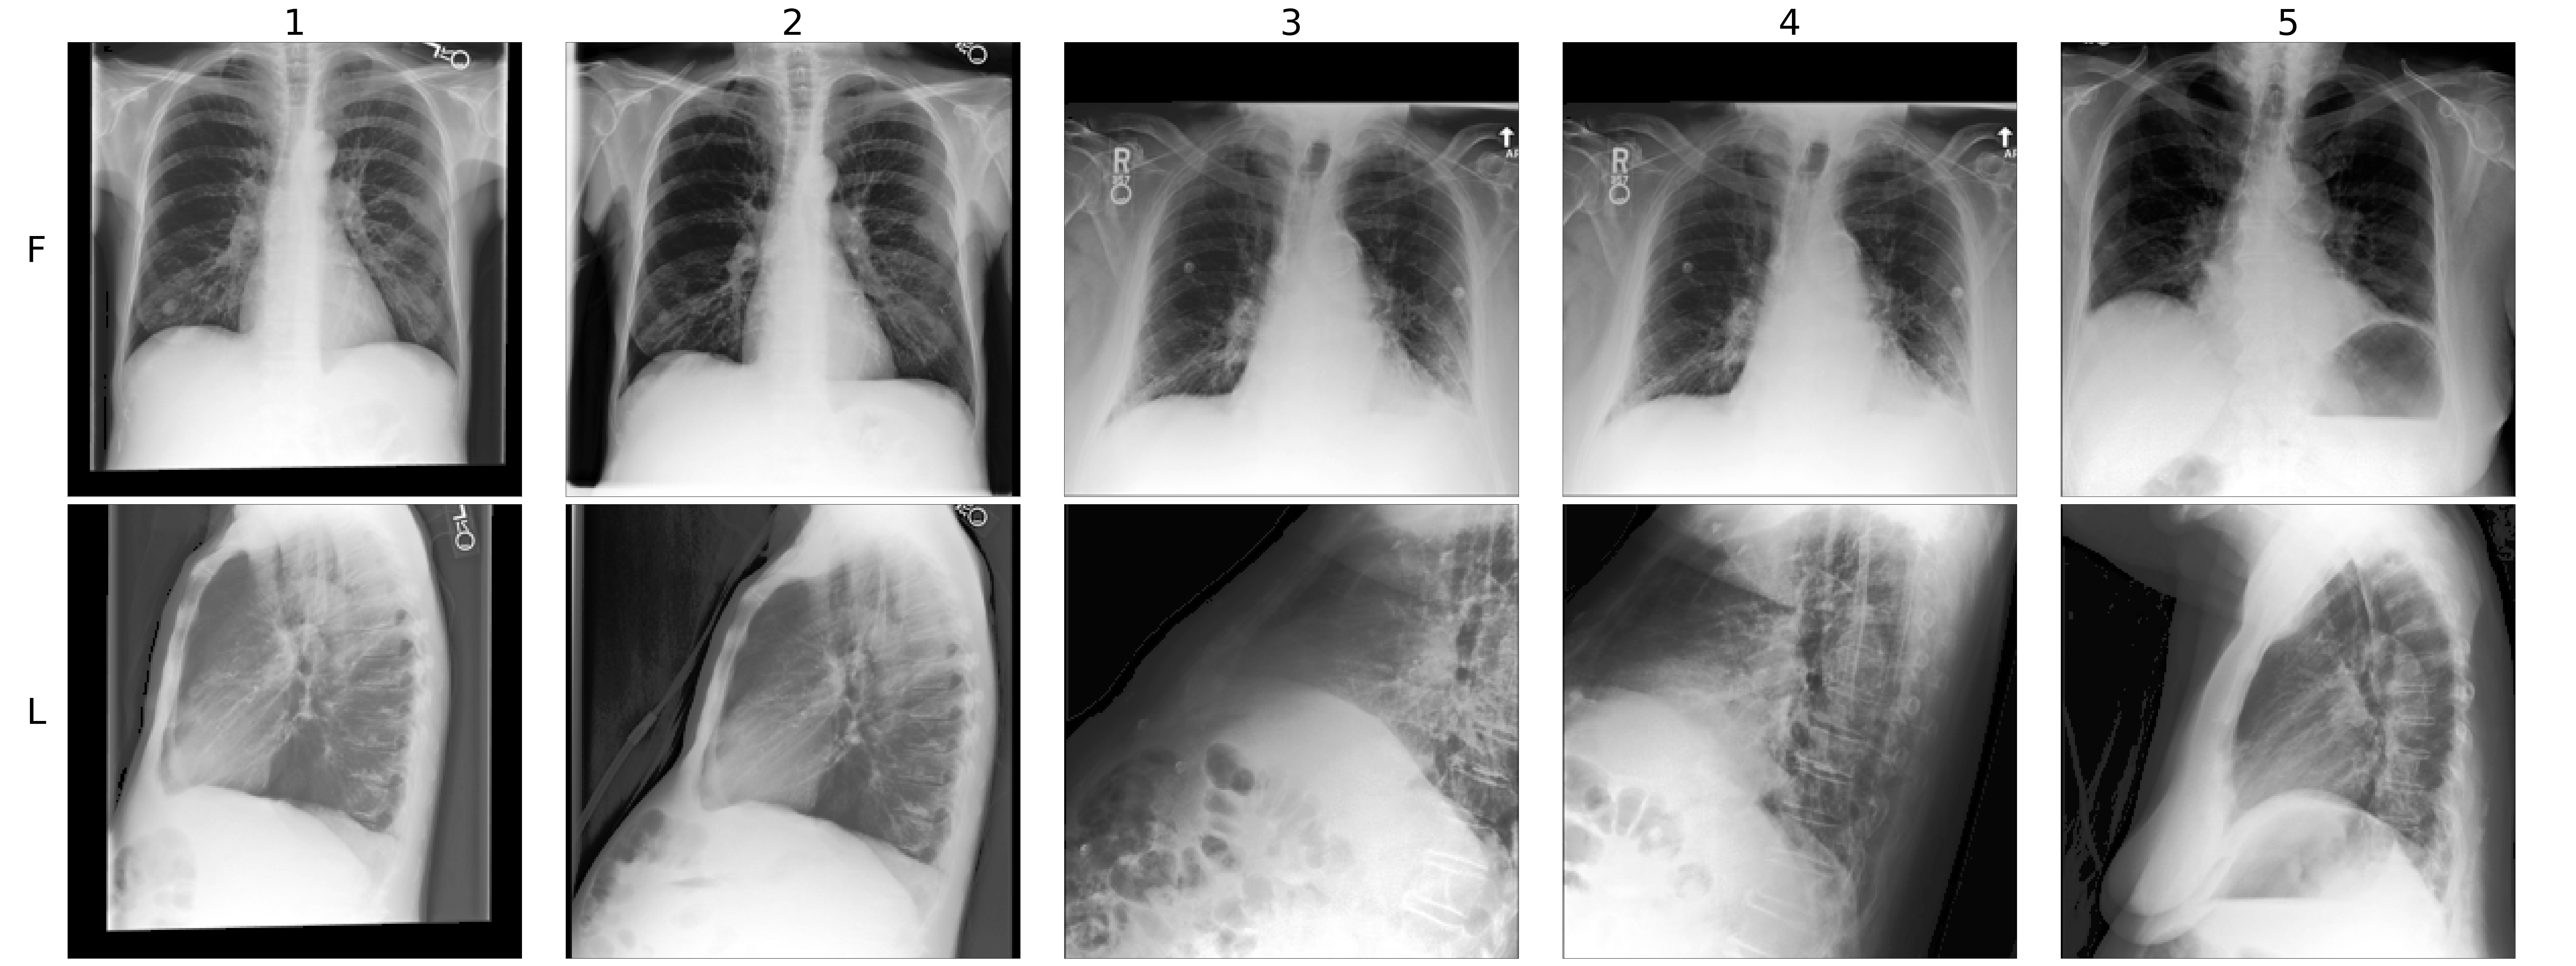

Dataset. To assess the performance of our approach in a real-world setting, we evaluate the proposed MMVM method on the automated analysis of chest X-rays, a common and critical medical task. For this purpose, we use the MIMIC-CXR dataset (Johnson et al., 2019b), a well-established and extensive collection of chest X-rays. The dataset reflects real clinical challenges with varying image quality due to technical issues, patient positioning, and obstructions. The dataset includes different views, which provide complementary information valuable for improving diagnostic (Raoof et al., 2012). In this work, we consider frontal and lateral images as two modalities (see Section B.7 for further details). Each set of X-rays is labeled with different cardiopulmonary conditions, which have been automatically extracted from the associated radiology reports (Irvin et al., 2019). This results in instances with incomplete label sets (Haque et al., 2023), which presents a challenge for fully supervised approaches and motivates the need for self-supervised methods instead.

Results. We assess the quality of the unimodal latent representations of the MMVM VAE by comparing them to those learned by independent VAEs and the PoE VAE (see Section 5.1). We do this by training binary random forest classifiers independently for each method and label on the inferred representations of a subset of the training set. Table 1 shows the AUROC for these classifiers, averaged over three seeds and both unimodal representations for a subset of labels. In addition, we also report the performance of a deep nonlinear network trained in a fully supervised manner on the same train/test split for reference purposes. Detailed experiment information can be found in Section B.7.3, with extensive results for each modality and label available in Table 2 and Table 3. Overall, our approach shows performance improvements across all labels compared to the other VAEs and is highly competitive with the fully-supervised method, surpassing it in average performance over all labels. Examining each unimodal representation separately provides further insights into the VAEs’ ability to leverage information from other modalities during training. For example, in the Cardiomegaly prediction task, the MMVM VAE’s lateral representations zLsubscript𝑧𝐿z_{L}italic_z start_POSTSUBSCRIPT italic_L end_POSTSUBSCRIPT slightly outperform the PoE VAE’s frontal representations zFsubscript𝑧𝐹z_{F}italic_z start_POSTSUBSCRIPT italic_F end_POSTSUBSCRIPT (MMVM zLsubscript𝑧𝐿z_{L}italic_z start_POSTSUBSCRIPT italic_L end_POSTSUBSCRIPT: 78.7%, PoE zFsubscript𝑧𝐹z_{F}italic_z start_POSTSUBSCRIPT italic_F end_POSTSUBSCRIPT: 78.5%), even though the lateral modality seems generally less informative (supervised xLsubscript𝑥𝐿x_{L}italic_x start_POSTSUBSCRIPT italic_L end_POSTSUBSCRIPT: 79.0%, xFsubscript𝑥𝐹x_{F}italic_x start_POSTSUBSCRIPT italic_F end_POSTSUBSCRIPT: 81.7%) for this task. The same observation can be made for other labels (see detailed results and discussion in Section B.7.3). This illustrates the MMVM VAE’s ability to soft-share information between modality-specific latent representations during training, thereby enhancing the representation quality of the weaker modality.